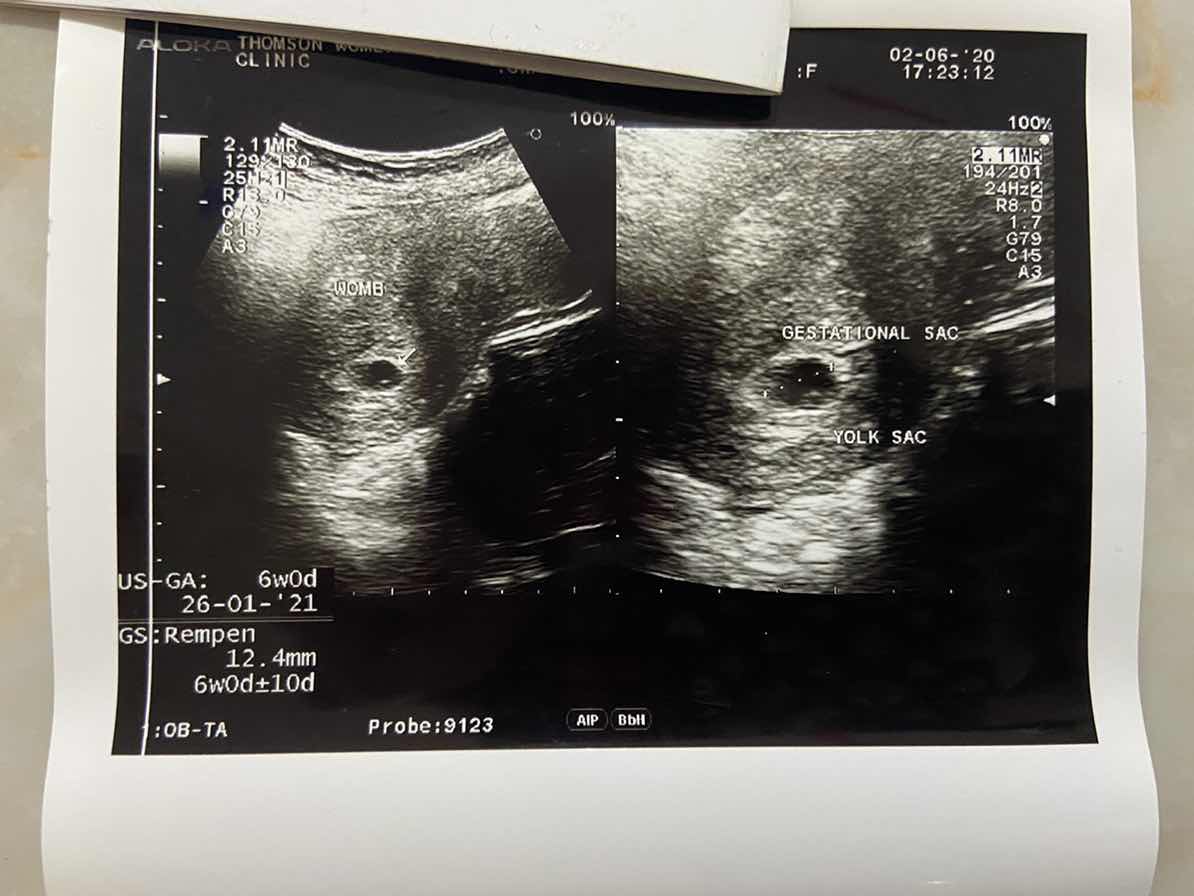

Hi, I'm 6 weeks pregnant today and i went to the doctor to get an ultrasound but the was nothing but a yolk sac seen is that normal? My last period on 17/04/20 and I had 2 miscarriage before so I’m kind of worried ? [23/06/20] Updated on my second ultrasound at 8~9 weeks My baby isn’t measuring where it should be and no heartbeat detected l...possible miscarriage??? No bleeding 🩸 or pain yet just feeling mild backache ☹️ 1st pic ultrasound scan on 2/06/20 2nd pic ultrasound scan on 23/06/20